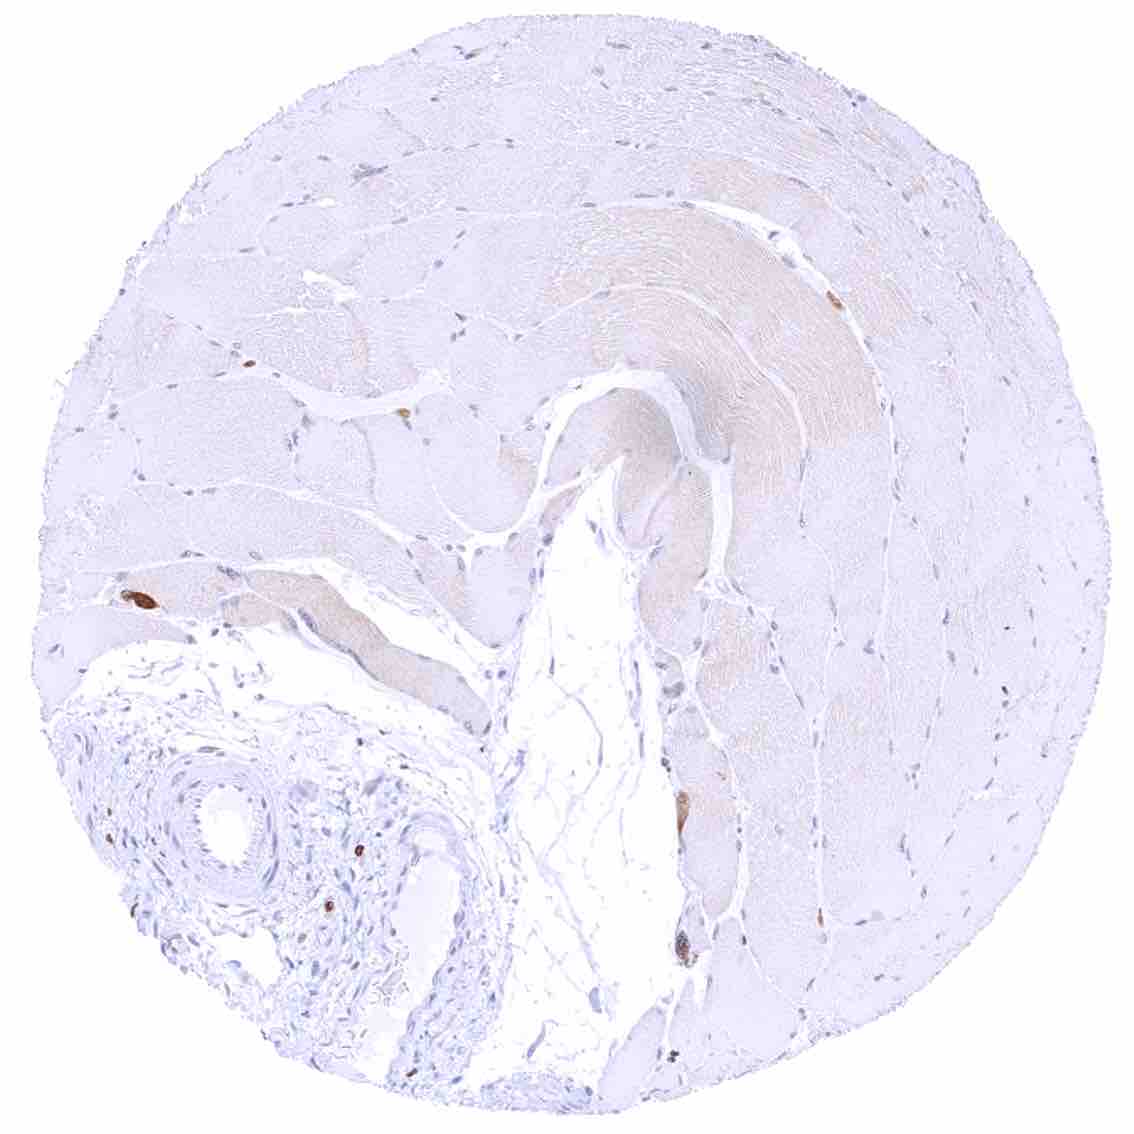

Uterus, myometrium – Weak to moderate cytoplasmic bcl-2 staining of smooth muscle fibers.